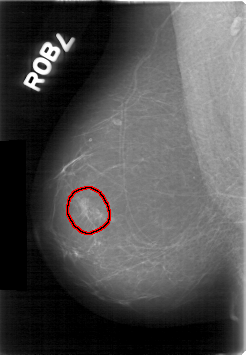

D_4020_1.RIGHT_MLO

FILE: D_4020_1.RIGHT_MLO.OVERLAY

TOTAL_ABNORMALITIES 1

ABNORMALITY 1

LESION_TYPE MASS SHAPE LOBULATED MARGINS OBSCURED

ASSESSMENT 0

SUBTLETY 2

PATHOLOGY BENIGN

TOTAL_OUTLINES 1

BOUNDARY